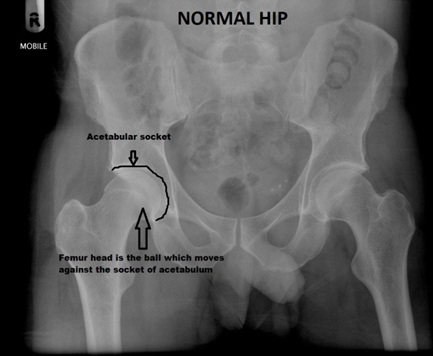

Hip replacement surgery, also known as hip arthroplasty, is a surgical procedure in which a damaged or diseased hip joint is replaced with an artificial implant. The surgery is primarily performed to relieve pain and restore function in patients with severe hip arthritis, osteonecrosis, fractures, or other degenerative conditions. Over time, conditions like osteoarthritis lead to cartilage deterioration, causing bones to rub against each other, leading to severe pain, stiffness, and reduced mobility. When conservative treatments fail to provide relief, hip replacement surgery becomes a final option to improve quality of life for patients.

Patients must evaluate the severity of their symptoms and consider alternative treatments before deciding on surgery. If conservative approaches such as medication, lifestyle changes, physiotherapy, and injections fail to provide relief, and pain significantly affects daily life, hip replacement may be the best solution. Consulting with an Orthopedic surgeon in Bangalore and reviewing X-rays or MRIs will help determine the necessity and timing of the procedure.